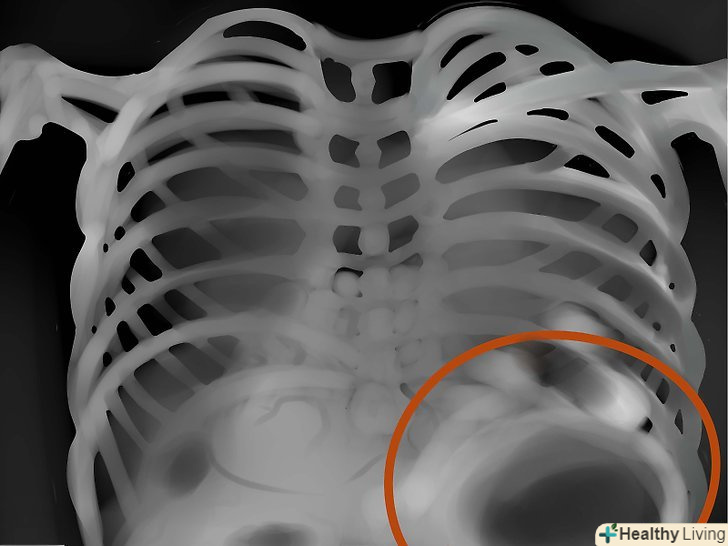

Діафрагми.придивіться, чи немає на знімку слідів плоскою або піднятою діафрагм, що може означати емфізему або пневмонію відповідно. Звичайно, не тільки їх. І врахуйте, що в нормі права діафрагма вище лівої - печінку піднімає. Реберно-діафрагмальний кут в нормі гострий, при асциті-тупий.